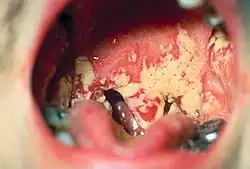

The main symptoms of ADA deficiency include pneumonia, chronic diarrhea, widespread skin rashes, jaundice (from hepatic infections), and candidiasis of the mouth and esophagus. Affected children also grow much more slowly than healthy children, commonly referred to as "failure to thrive," which may lead to other developmental delays.[4]